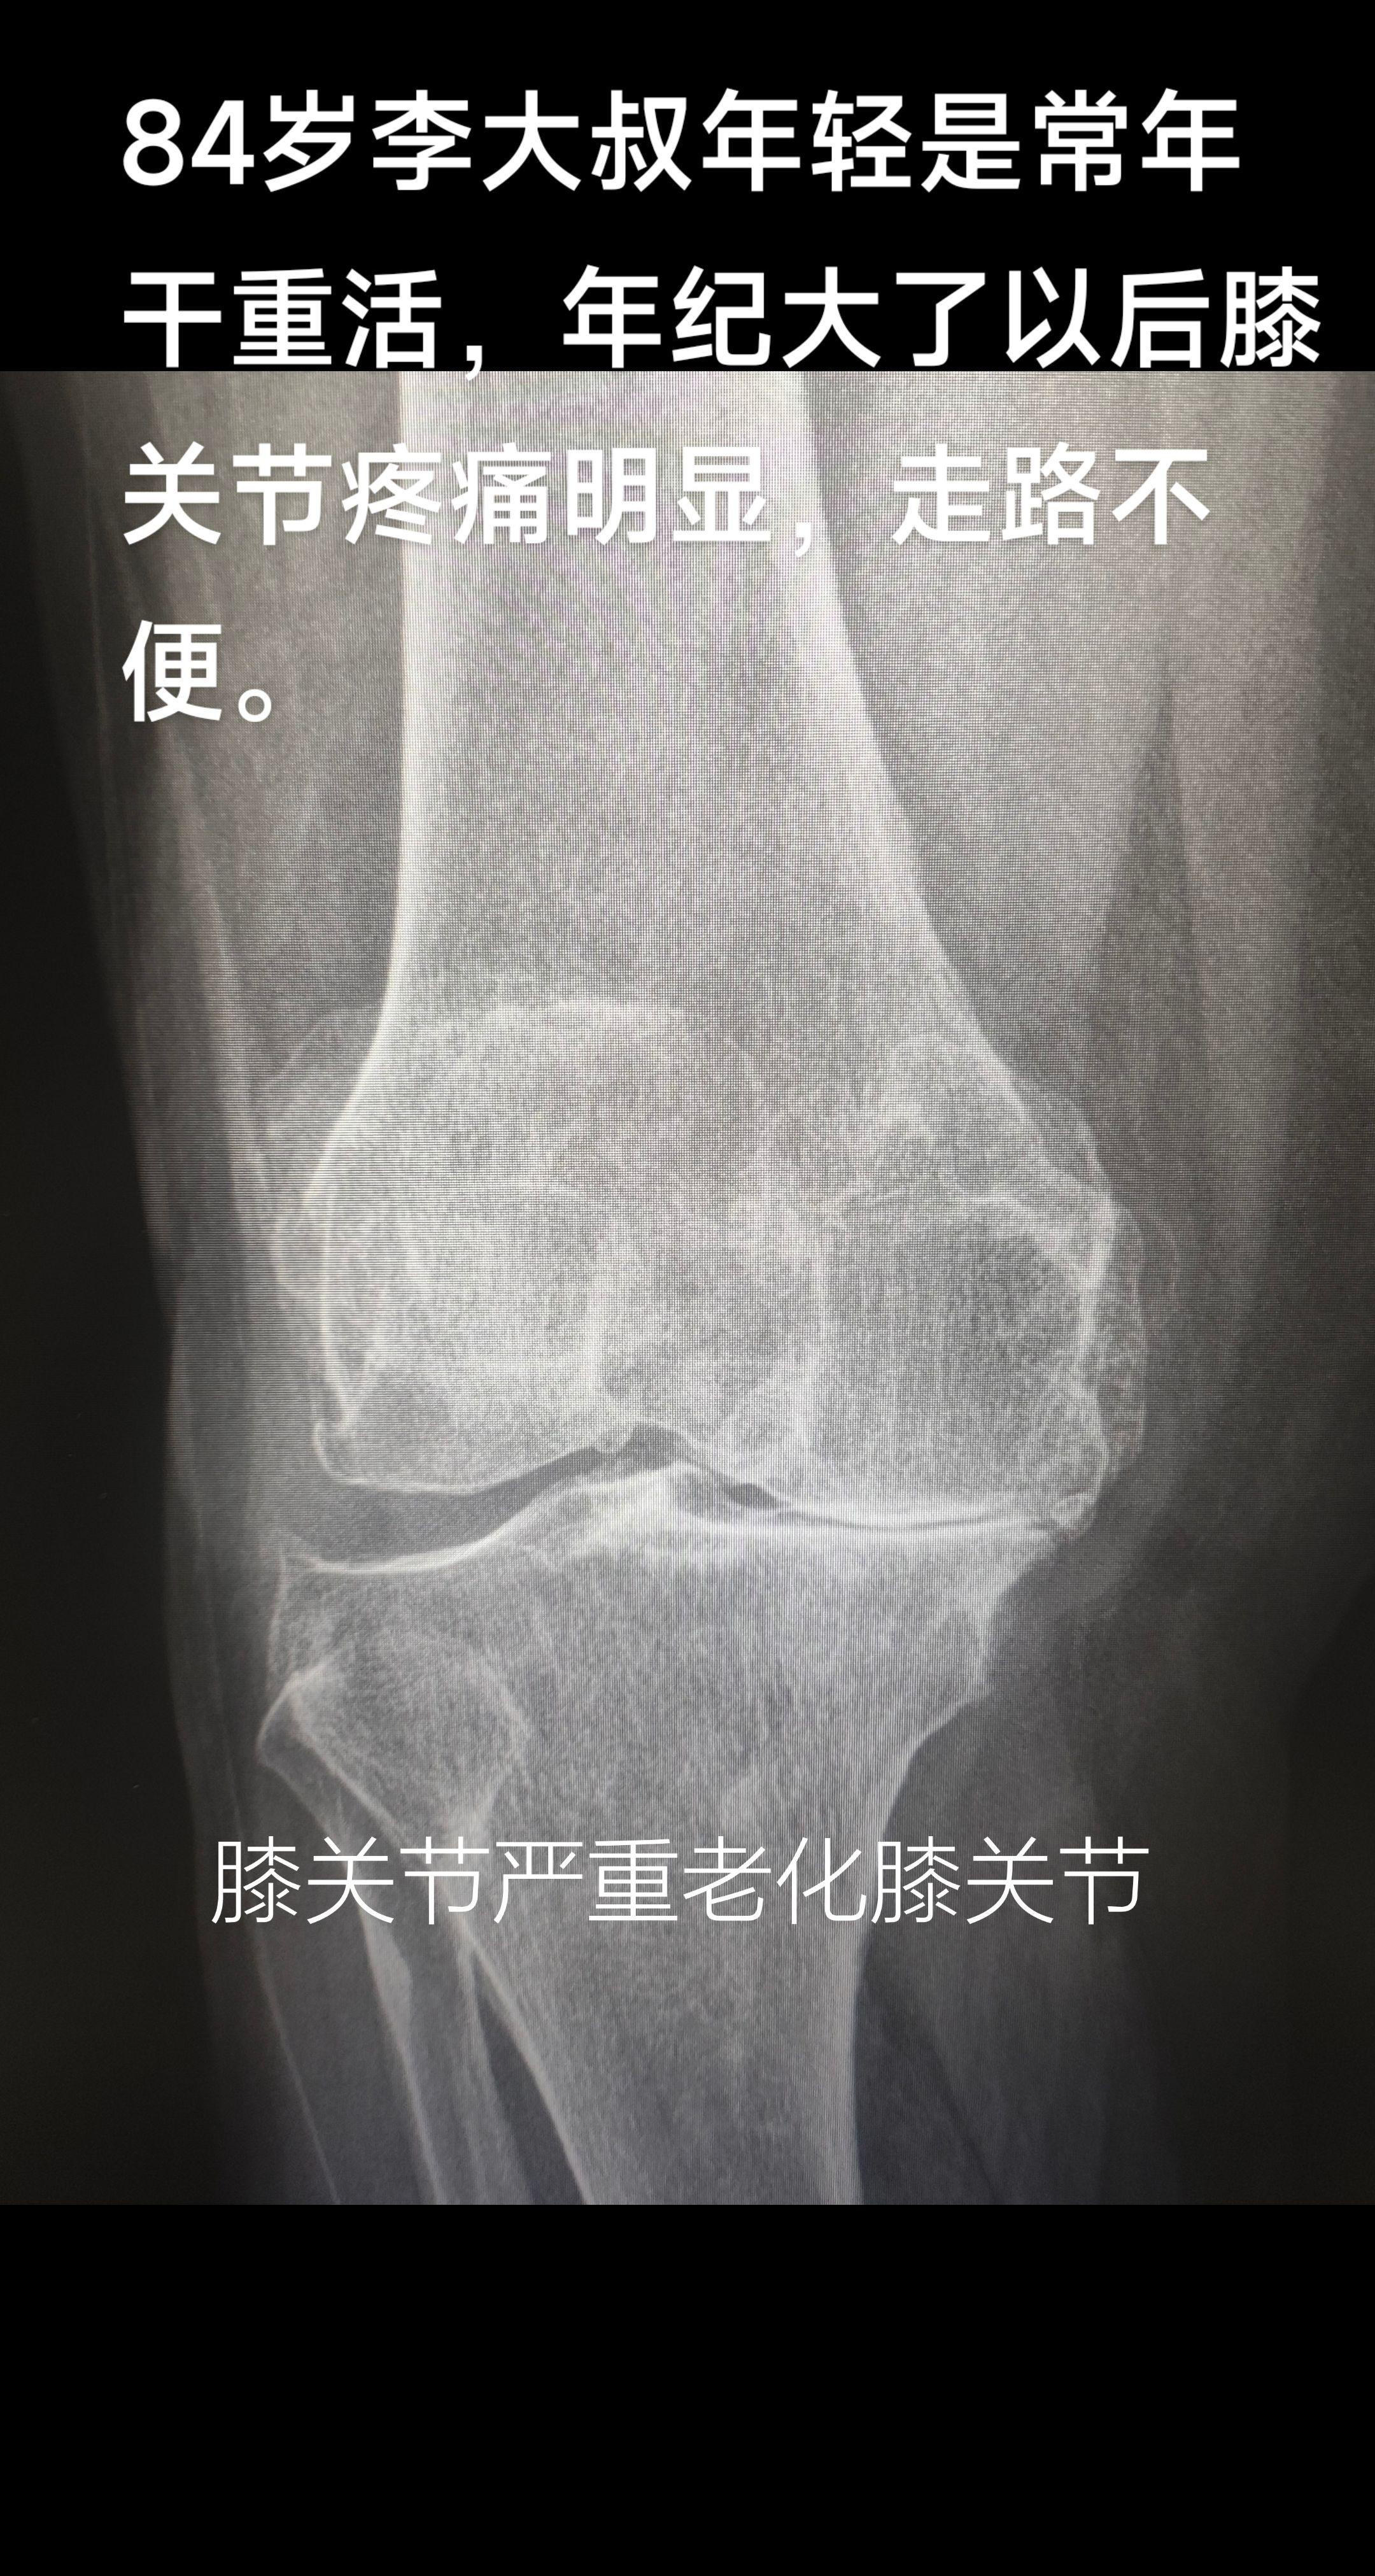

膝关节痛。